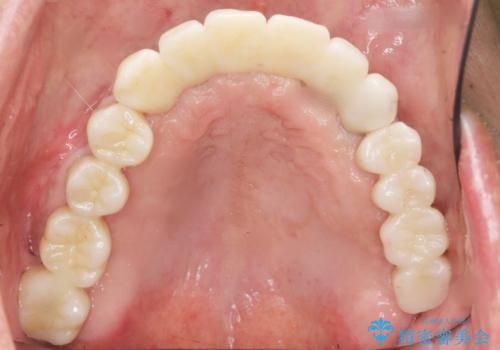

当初は上顎③2①12③ブリッジの予定でしたが、リカバリー手術後上顎3②11②③ブリッジによる補綴を行いました。

- ¥1,738,000 (骨増生、インプラント×3本、リカバリー手術、アバットメント×3本、仮歯×6本、クラウン×6本) ※税込費用は治療当時の料金となります

リカバリー手術により無事に治療が終わりご安心頂けました。

インプラントの種類:スプラインツイスト(HAコーティング)

固定様式:セメント固定

クラウンの種類:ベレッツァクラウン